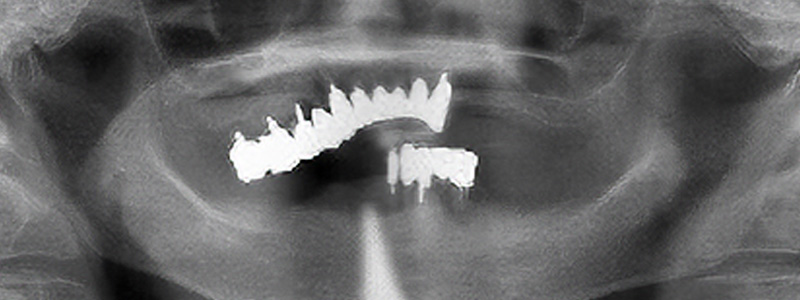

- 治療名

- インプラントオーバーデンチャー

- 治療内容

- 下顎にインプラント・入れ歯治療

- 患者様

- 70代女性

- 治療期間

- 9ヶ月

- 費用

- ¥2,035,000

- 治療に対するリスク

- 外科処置に対する疼痛合併症のリスク

- 執刀医

- Dr.村尾